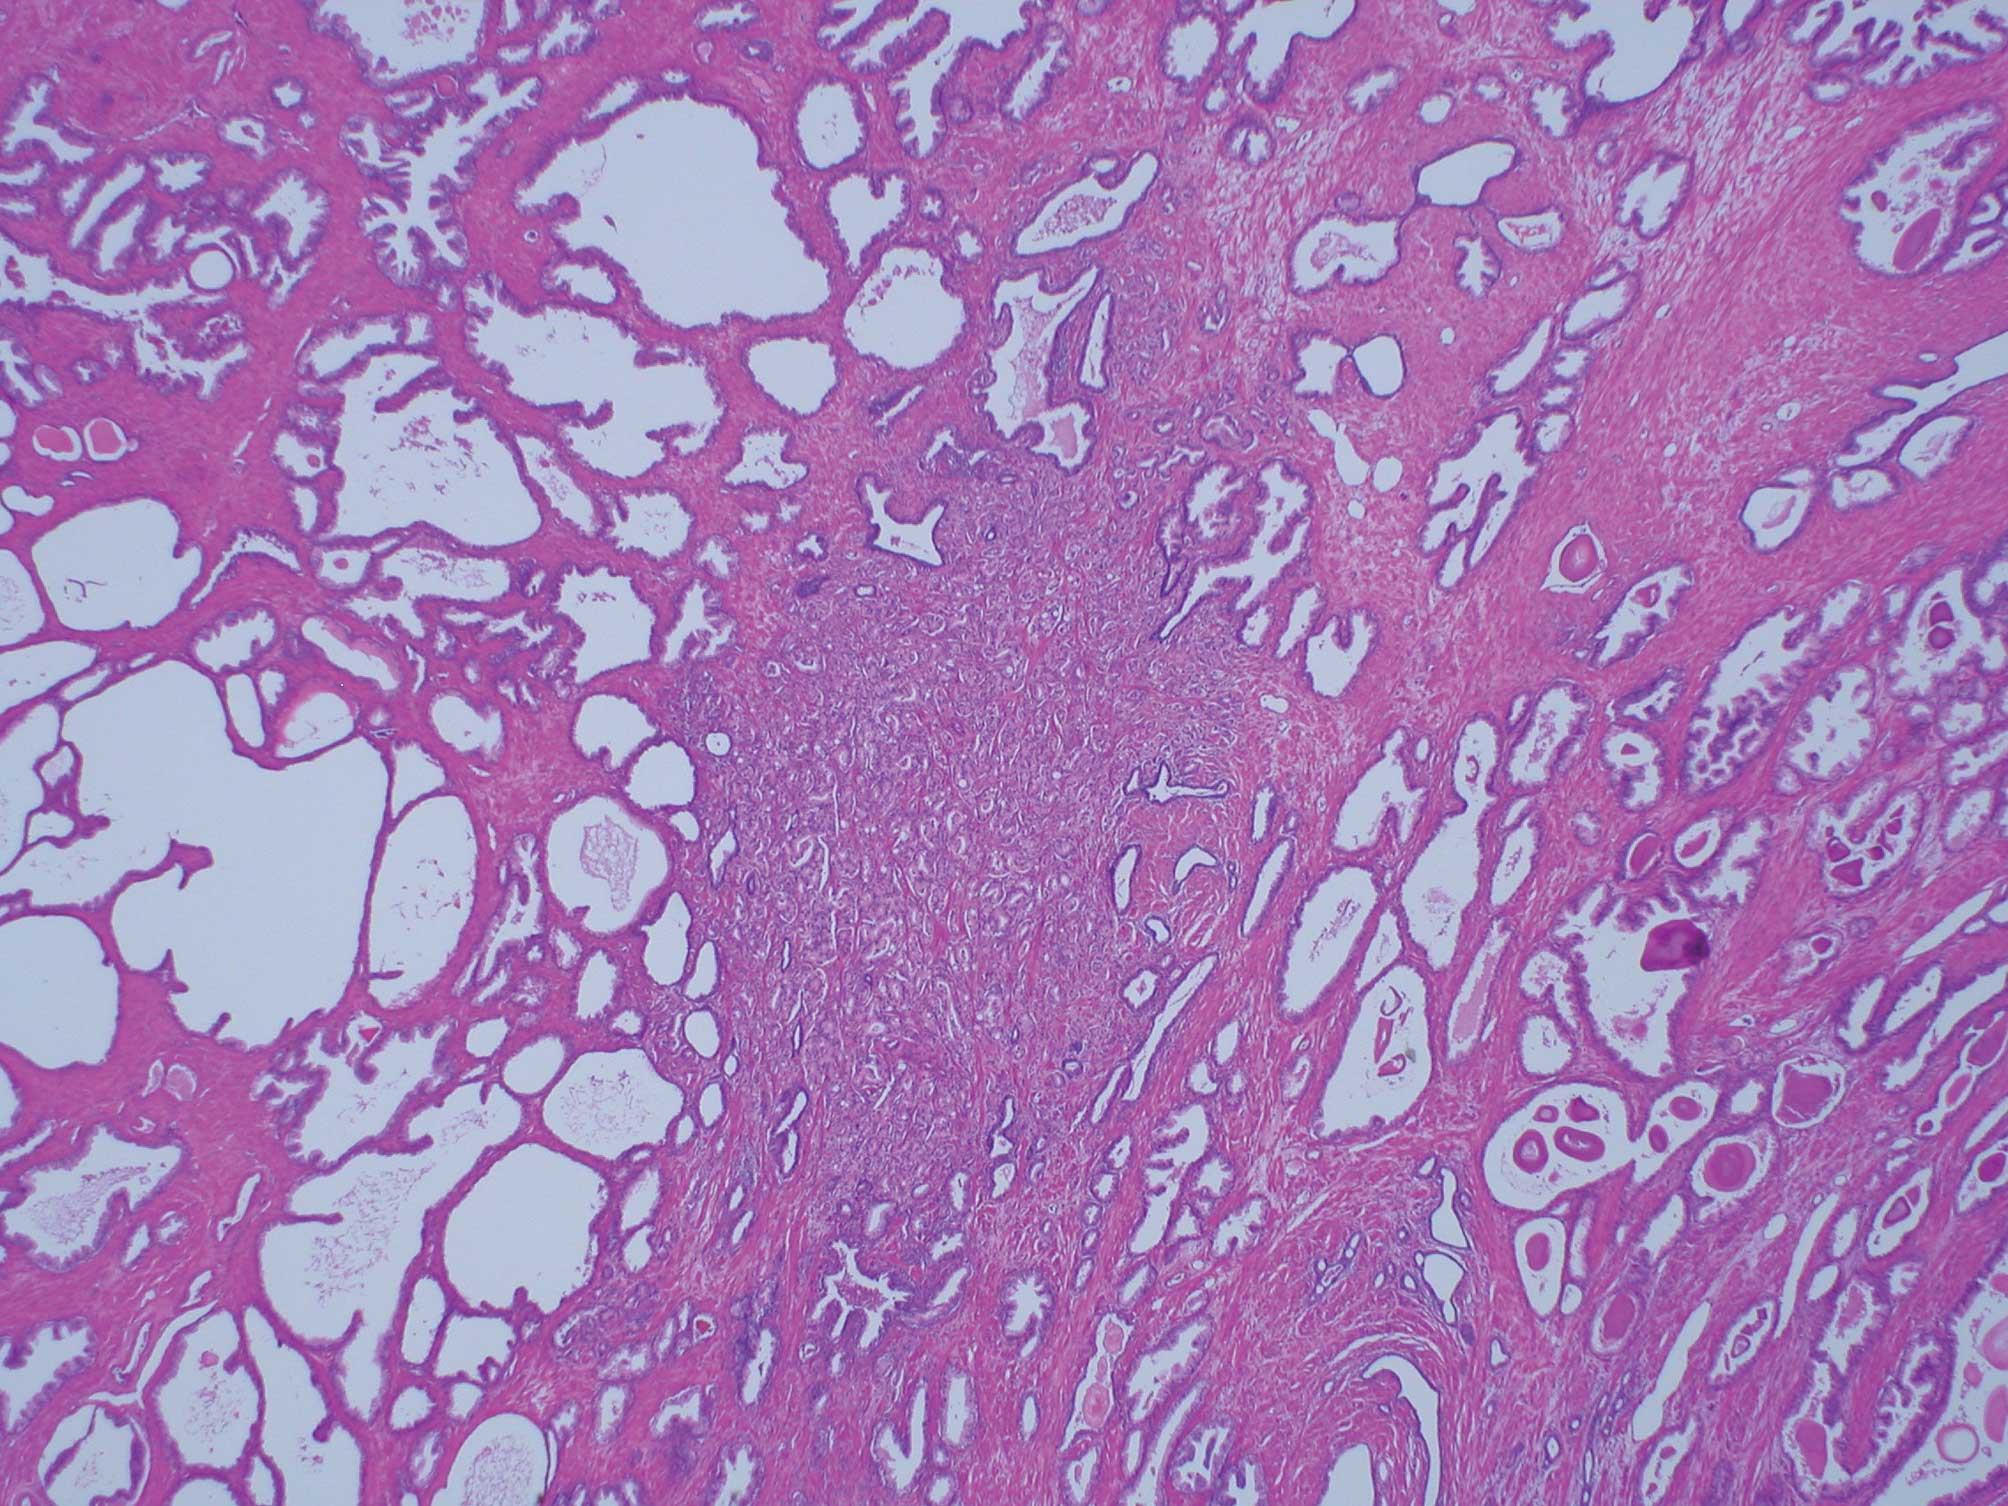

In an evaluation of the Gleason primary pattern, 45 cases with a cancer volume of <0.5 cm3, or 64.4% of the lesions, exhibited Gleason pattern 3, while Gleason pattern 4 was observed in 26.7%; a total of 91.1%. When lesions with Gleason pattern 5 were included, the Gleason primary pattern totaled 95.5% (Table I). Similarly, secondary Gleason patterns 3 and 4 were observed in 53.3 and 42.2% (a total of 95.5%) of cases, respectively, for lesions with a cancer volume of <0.5 cm3. The Gleason secondary pattern included 97.7% when the lesions with Gleason pattern 5 were included (Table II). In addition, no cribriform carcinoma was identified in Gleason pattern 3 in lesions with a cancer volume of <0.5 cm3 (Table III). In the group with a cancer volume <0.5 cm3, both the Gleason primary and secondary patterns were consistent with a carcinoma with a small size acini. When the density of those acini was compared with that of ambient normal acini, it proved to be much higher (Fig. 1). With the increase in total cancer volume, Gleason primary pattern 4 and the cribriform carcinoma classified as Gleason pattern 3 increased significantly (p<0.01; Tables I and III), while the Gleason primary pattern 3 alone decreased (p<0.01; Table II). Over 95% of the total cancer volume ≥1 cm3 contain cribriform carcinoma classified as Gleason pattern 3.

Figure 1

Dense prostatic carcinoma in comparison with non-neoplastic acini.

To demonstrate the original patterns of prostatic carcinoma, lesions with a cancer volume of <0.5 cm3 were evaluated using the definitions of insignificant cancer described by Stamey et al (5). Gleason primary patterns 3 and 4 accounted for 91.1% of the smaller tumors, while Gleason secondary patterns 3 and 4 were found in 95.5% of the lesions. These data indicate that the classification of prostatic carcinoma with a cancer volume of <0.5 cm3 is predominantly Gleason pattern 3 and 4. In this group, Gleason pattern 3 did not exhibit a cribriform pattern and consisted of assembled acini, which were independent and smaller in size than those characteristic of Gleason patterns 1 or 2. Gleason pattern 4 exhibited independent and ill-defined acini and did not contain large cribriform acini. In other words, the acini of prostate carcinoma with a cancer volume of <0.5 cm3 consisted mostly of independent acini of a small size. Furthermore, these acini proliferated without disrupting the structure of smooth muscle. The acini were quite dense in comparison to the surrounding non-neoplastic acini (Fig. 1). Based on these observations, it would appear that small acini of prostatic carcinoma are dense because they invade not only the surrounding acini and small ducts, but also the stroma at a quite early stage. Humphrey reported that the natural history of prostatic carcinoma begins with the invasion of prostatic carcinoma cells in the stroma. Most prostatic carcinomas fail to elicit a stromal response. Subsequently, the malignant acini appear to be embedded within normal-appearing fibromuscular stroma (6). These descriptions are consistent with observations in the present study. Prostatic carcinomas originate morphologically in independent small-sized acini. Therefore, prostatic carcinomas are dense in comparison with non-neoplastic acini because of the invasion not only into the surrounding acini and small ducts, but also in the stroma at a relative early stage.